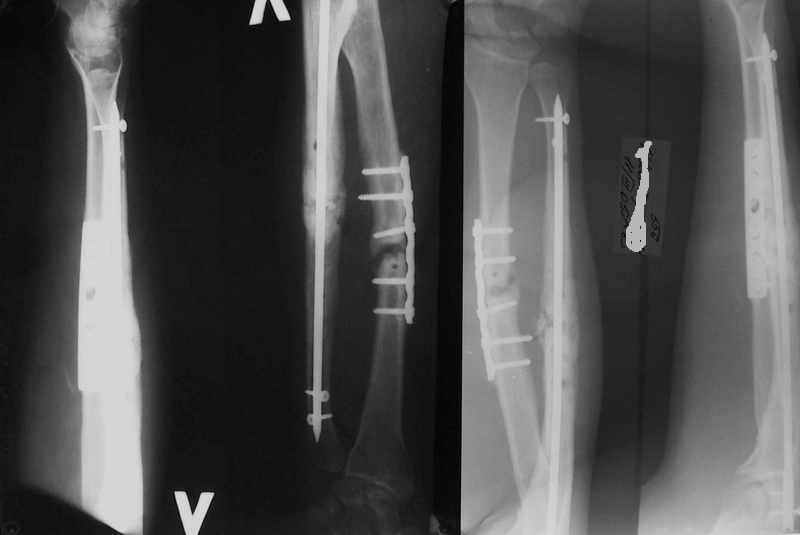

А зачем же неправильный гвоздь использовать, который нарушает? Наоборот, с помощью гводя нарушенная форма костей очень даже эффективно восстанавливается (см. пример). А неправильный

>Наоборот, с помощью гводя нарушенная форма костей очень даже эффективно восстанавливается (см. пример).

форма восстанавливается, но достаточной стабильности при таком остеосинтезе (пример) достигнуть трудно, ранние движения невозможны, а несращения встречаются как и при любом виде остеосинтеза.

При *закрытом* интрамедуллярном остеосинтезе - это редкость. Где-то на 60 больных есть одно несращение лучевой кости (рентгенологическая находка, клинических проявлений нет) - синтез получился с удлинением.

Ну и мы сейчас как раз несращения после других видов остеосинтеза интрамедуллярными стержнями фиксируем...